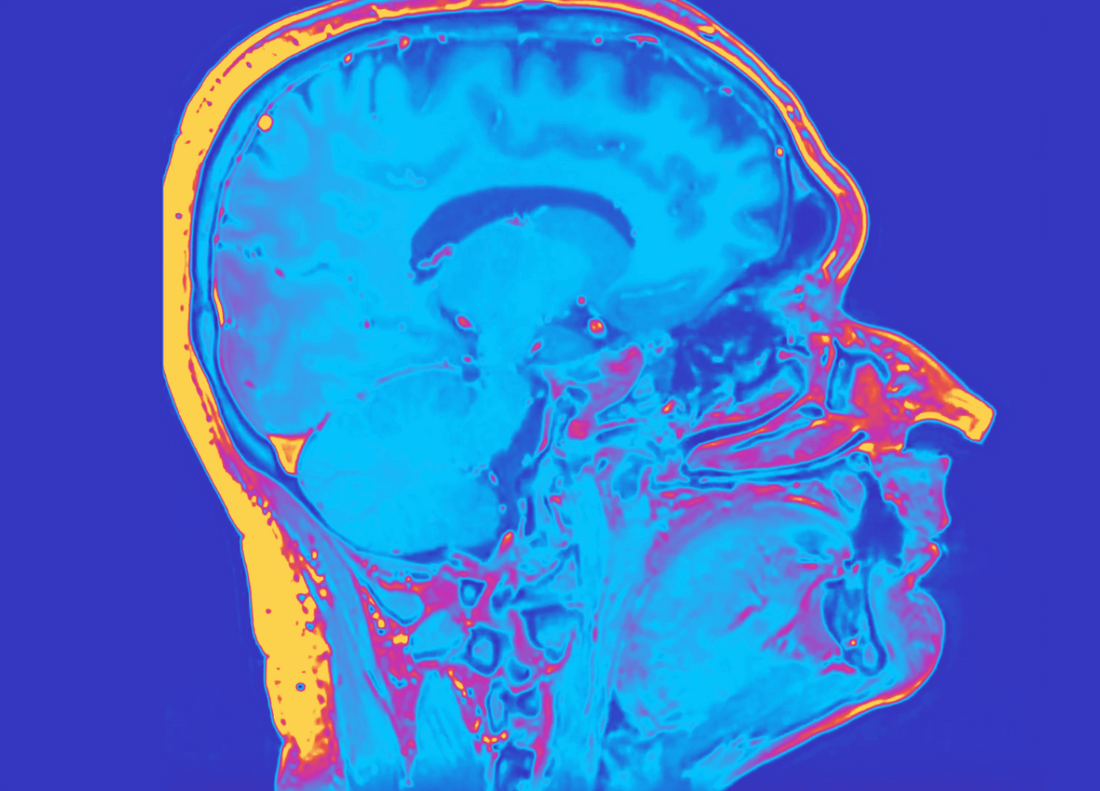

Recap of the neurobiology behind ADHD (1, 2)

ADHD is linked to alterations in key neurotransmitters systems - notably dopamine and noradrenaline.

• Dopamine is linked to cognitive functions like reward processing and attention.

• Noradrenaline is linked to working memory.

In ADHD, dopamine is cleared away from brain synapses more quickly than usual, as ADHD brains have higher dopamine reuptake transporters.

This means there’s less dopamine available to pass messages between neurones, making it harder to sustain focus, regulate impulses, and initiate tasks.